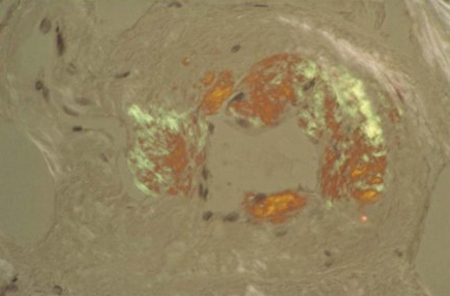

Deep rectal biopsy is necessary to confirm a diagnosis of suspected gastrointestinal amyloidosis.[Figure caption and citation for the preceding image starts]: Congo red stain blood vessel in a bone marrow biopsy demonstrating green birefringence pathognomonic of amyloidosisCourtesy of Morie A. Gertz, MD/Mayo Clinic; used with permission [Citation ends].